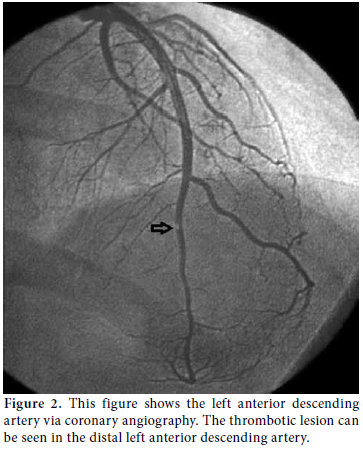

During the clinical follow-up period, the patient's ECG showed dynamic anterior ST-T changes in the precordial derivations (Figure 1), and repeat measurements of these markers revealed a typical course of ACS that featured a relevant rise and fall in TnI. Therefore, the patient underwent coronary angiography which revealed a distally occluded left anterior descending coronary artery (Figure 2). Percutaneous transluminal coronary angioplasty was performed on the occluded site, and because of the thrombotic view of the lesion with a remnant of 30% stenosis accompanied by thrombolysis in myocardial infarction (TIMI) three flow, medical therapy with tirofiban infusion was prescribed for up to a period of 24 hours instead of stent implantation.

Consultations were then held with the pulmonary medicine and rheumatology departments regarding the eosinophilia identified in the CBC, pulmonary opacities revealed via chest X-ray, and the patient's past history of asthma (Figure 3). Furthermore, cranial computed tomography (CT) was performed on the day after the angiography which showed neurological involvement or paranasal sinus abnormality with a prediagnosis of CSS. The results of the cranial CT were also consistent with chronic sinusitis. The presence of asthma, hypereosinophilia of >10%, chronic sinusitis, and pulmonary opacities represent four of the six ACR criteria required for the diagnosis of CCS.[5] Our patient tested negative for anti-nuclear antibodies (ANAs), anti-double stranded DNA (antidsDNA), extractable nuclear antigens (ENAs) and anti-neutrophil cytoplasmic antibodies (ANCAs). The corticosteroid methylprednisolone at an initial dosage of 80 mg per day (1 mg/kg/d) was prescribed after the termination of the tirofiban infusion. Afterwards, the patient's eosinophil levels in the CBC decreased to normal ranges, and symptomatic relief was completely provided. Control coronary angiography was performed one week later, and the thrombotic lesions had disappeared (Figure 4). In addition, chest radiographs showed complete resolution of the opacities (Figure 5). After two more weeks, control echocardiography was performed revealing a normal morphology of the ventricles without any segmental wall motion abnormalities. Furthermore, the pericardial fluid had also disappeared.